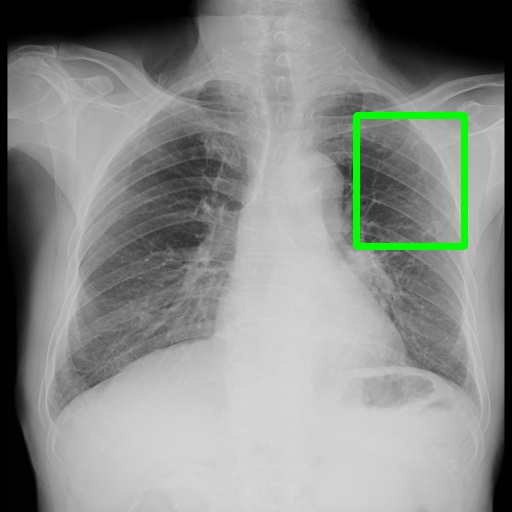

6.4 Visualization

To gain insights into the learning process of deep neural networks on CXR images, we visualize the feature map of SymFormer w/ RetinaNet at a scale of . To achieve this, we employ principal component analysis (PCA) to reduce the channels of the feature map to a single channel. The resulting single-channel map is then converted into a heat map for visualization purposes. The visualization of the learned features, along with the corresponding detection results, are presented in Fig. 6. Upon analysis, we observe that the visualization of healthy cases exhibits irregular feature patterns, indicating the absence of significant abnormalities. In contrast, the visualization of sick but non-TB cases displayed some discernible highlights, potentially representing the presence of lesions. For TB cases, the highlights in the visualization map align well with the annotated TB infection areas, thereby indicating the effectiveness of the proposed SymFormer in learning deep features for TB area detection. Furthermore, in Fig. 7, we offer qualitative comparisons between the proposed SymFormer and the baseline models for TB infection area detection. As evident, SymFormer consistently delivers superior qualitative detection results.